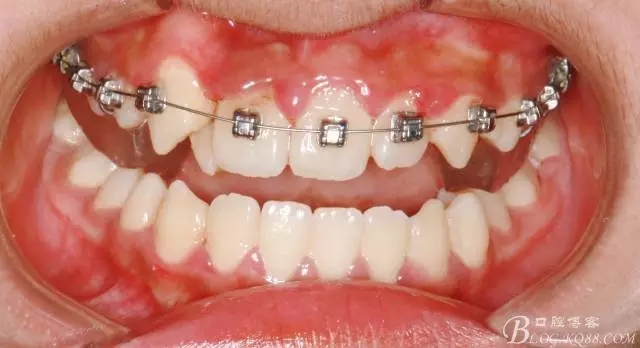

前牙反合伴擁擠的案例

通常情況下,前牙反合的患者因上頜發(fā)育不足,會(huì)伴發(fā)上頜前牙區(qū)牙列擁擠;

患者13歲,男性,自覺(jué)牙齒不齊要求矯正;

在活動(dòng)頜墊輔助下打開(kāi)咬合,并對(duì)上頜排齊、擴(kuò)弓;

此期間要避免前牙咬合干擾;